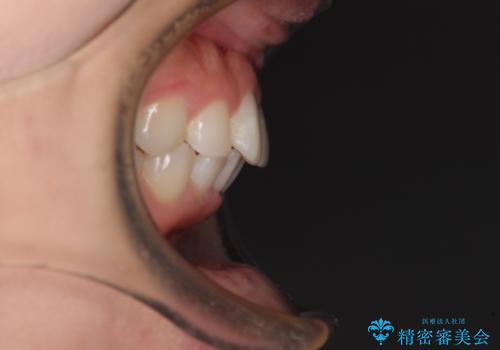

矯正治療の後戻り ガタガタになった前歯の部分矯正

- 以前の矯正治療の後戻りを気にして来院された患者様です。

下顎前歯にデコボコがあるため、ワイヤー矯正により改善することとしました。